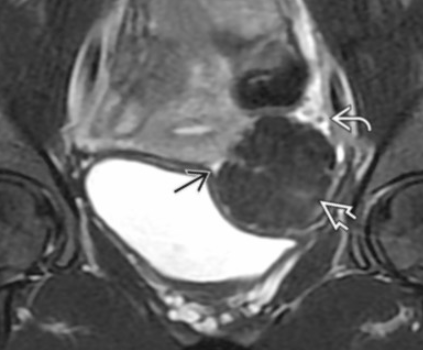

Endometrioma

• T2 dark

• T1 bright

• T1FS-bright

• Has internal T1 hyperintensity from old blood

• On US

• No color on doppler